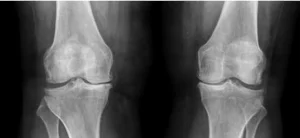

A artrose de joelho é uma doença que acomete uma porção considerável da população e demanda tratamentos específicos. Em muitos casos, até cirúrgicos. Mas quando a cirurgia para artrose de joelho é indicada? Como ela é feita e quais as técnicas?

Pacientes com artrose de joelho com comprometimento progressivo da independência das atividades de vida diária, dor e falha do tratamento conservador devem ser indicados para a realização do tratamento cirúrgico.